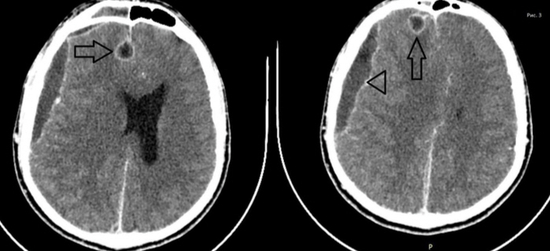

경막하농양(삼각)과 뇌농양(화살표시) MRI 영상경막하농양의 위치는 전두엽 부위에 많은데 대뇌표면을 따라 전파되거나 산발적인 농양이 형성됩니다.초기에는 수막염 증상을 보였으나 급속히 악화되어 의식 저하, 편마비, 발작을 볼 수 있습니다.뇌농양의 경우 크기가 커지면 뇌압의 상승과 함께 대뇌 탈출, 농양 파열로 사망에 이를 수 있습니다.